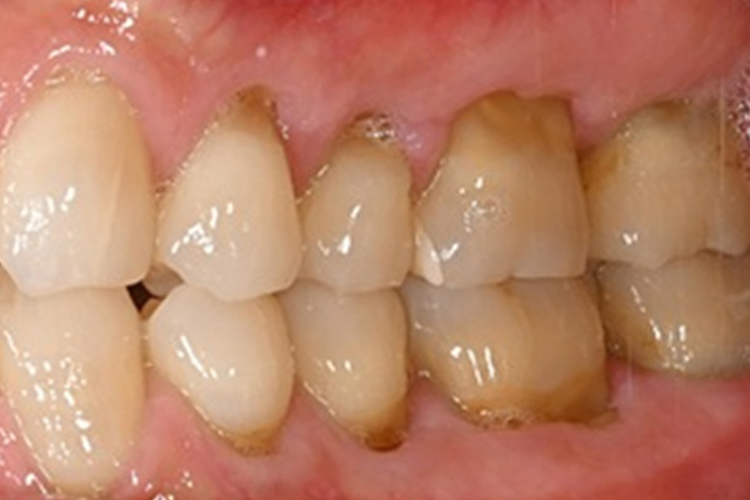

この患者様は、スケーリングより歯周ポケットが6mm以上ある患者様で患者様ご本人も歯周病になりかけている自覚がありました。また、口臭も気になされていましたので、ブルーラジカルの適用症例と判断し、施術を行いました。

施術前のレントゲンと口腔内写真です。